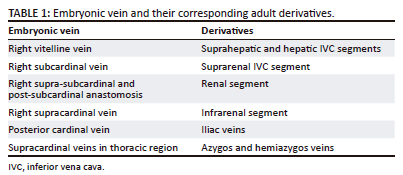

A left-sided IVC is formed as a result of disappearance of the right supracardinal vein and persistence of the left supracardinal vein. The left-sided IVC typically terminates at the left renal vein. It then courses ventral to the aorta to the right side to form a normal right-sided suprarenal IVC (Figure 1). The reported incidence is 0.2% - 0.5%.1,14,15 It is a mirror image variant without an increased risk of any abnormality. However, it can lead to confusion between venous and arterial access. Also, transjugular IVC filter placement and pulmonary thrombolysis is more challenging with a left-sided IVC. In addition, it can mimic left paraaortic adenopathy.1,9 Rare spontaneous rupture of an abdominal aortic aneurysm into a left IVC has also been reported.16,17